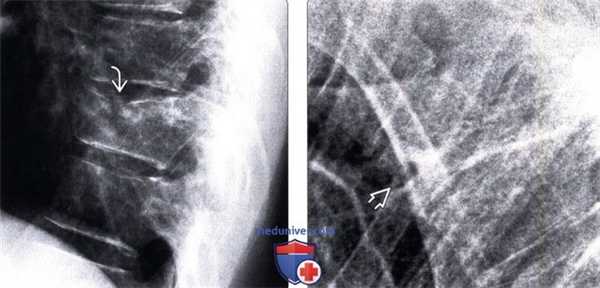

(Слева) Рентгенограмма в боковой проекции: угловая деформация верхней замыкательной пластинки Т10. Отмечается лишь минимальное снижение высоты переднего отдела тела позвонка.

(Справа) На рентгенограмме в боковой проекции определяется компрессионный перелом Т3. Переломы на этом уровне увидеть достаточно нелегко, однако при усилении кифоза их всегда следует подозревать.